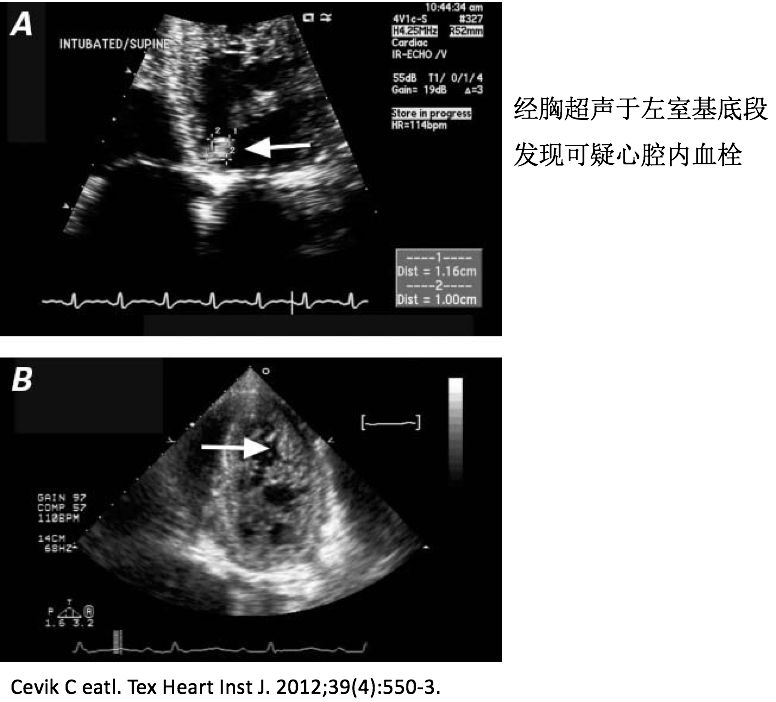

➤ (三)血栓事件

• 血栓形成的机制可能是与左心室腔内有多个深陷隐窝及增多的网格状肌小梁有关,导致血流速度减慢,容易形成附壁血栓,血栓脱落导致体循环栓塞。心腔内、脑血管以及肠系膜血管是常见栓塞部位

17岁男性因心源性卒中就诊.入院后行Echocardiography and cardiac MRI检查